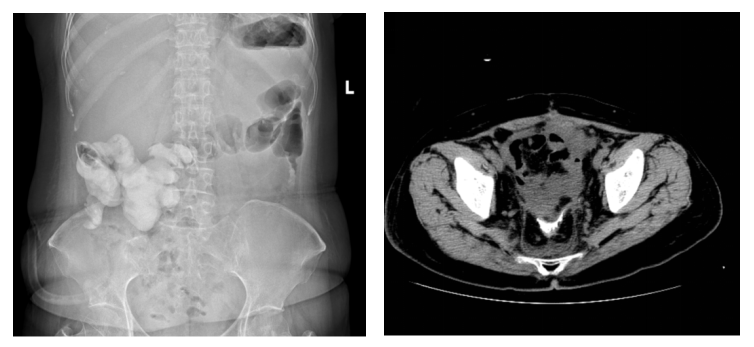

在妇科肿瘤外科、营养科及护理团队的通力合作下,患者邓女士术后恢复迅速,顺利进食,转流管引流通畅。术后复查显示支架位置良好,肝肾功能等指标稳定,并于术后第三周如期开始了首次静脉化疗。术后第四周,影像学证实支架已完全降解,转流管成功拔除,患者进食半流质后一切正常,吻合口愈合良好(如图4)。

图4:术后腹部平片可见小肠支架完全降解(左)/肠道造影发现吻合口愈合良好(右)